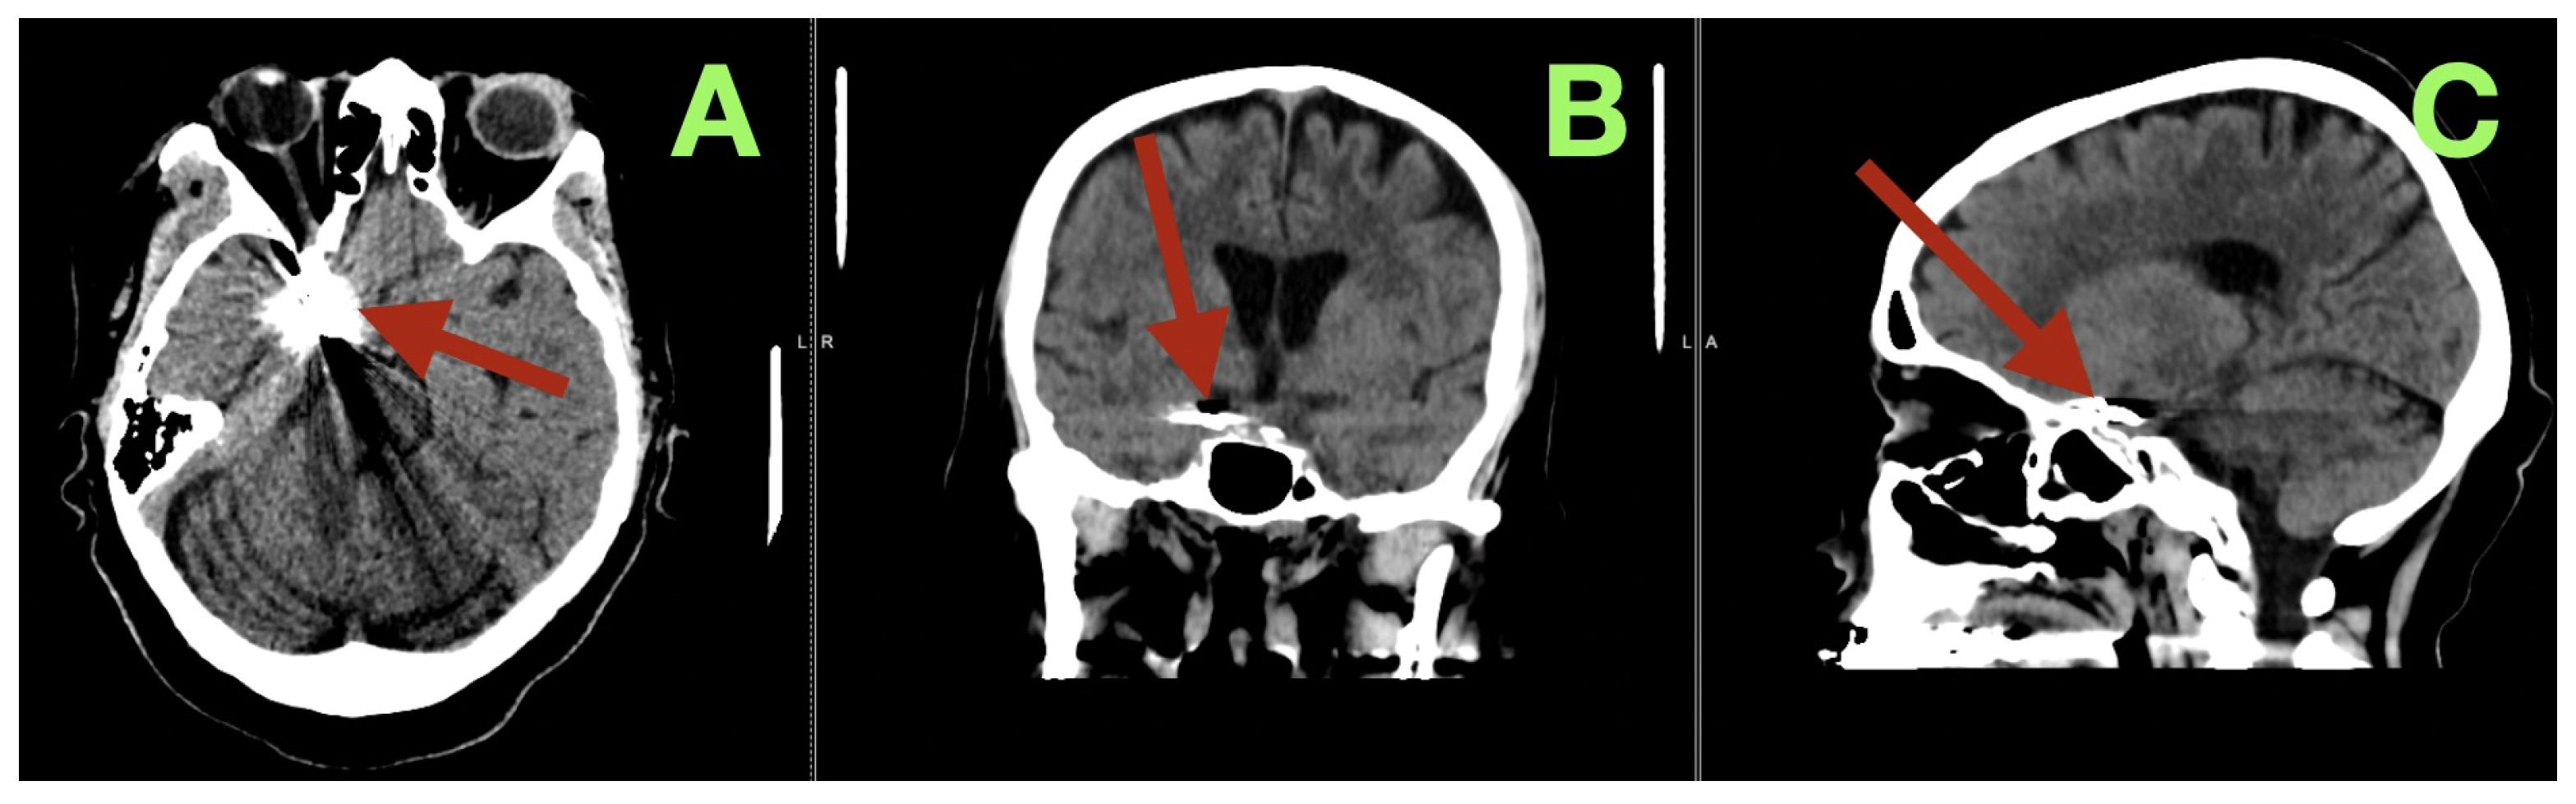

At the three-month follow-up evaluation, the patient reported resuming all of her daily activities without experiencing recurrent severe headache, confusion, or seizure-like episodes. The patient’s neurological examination was normal (all cranial nerves intact; pupils equal/reactive; normal eye movements without ptosis/diplopia; strength 5/5; stable gait; normal coordination). The patient’s MoCA score was 28/30. The patient’s functional outcome was mRS 0, and her Barthel Index was 100. Three-month CT angiography (Figure 4A–C) demonstrated complete aneurysm exclusion, a reconstructed patent carotid–PCom junction without parent vessel stenosis, no clip migration, and robust filling of the fPCA via the preserved PCom. There was no evidence of chronic ischemia, and the CSF spaces were restored without hygroma or hydrocephalus.

Figure 4.

Three-month postoperative control CT angiography. (A) Axial source image at the level of the skull base demonstrates the aneurysm clip at the right carotid–posterior communicating junction (arrow), with stable positioning and no surrounding hypodensity, hemorrhage, or parenchymal distortion. The adjacent temporal and basal frontal regions show preserved attenuation, without signs of delayed ischemic injury. (B) Coronal reconstruction confirms durable anatomical restoration of the parasellar and suprasellar region (arrow), with normal ventricular configuration and no evidence of hydrocephalus, mass effect, or clip-related compromise of adjacent structures. (C) Sagittal reconstruction localizes the clip construct along the reconstructed carotid–posterior communicating complex (arrow), illustrating maintained skull-base anatomy, absence of clip migration, and stable postoperative remodeling of the surgical corridor.